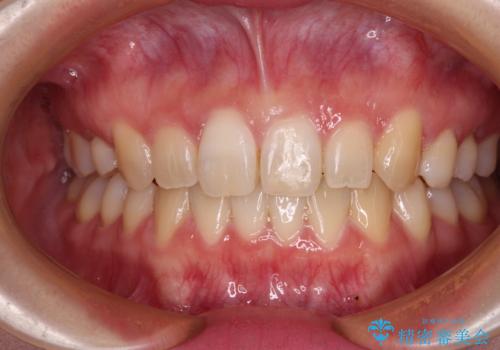

抜歯矯正を行ったことで、顎先のつっぱり感や口元の閉じにくさを解消することができました。